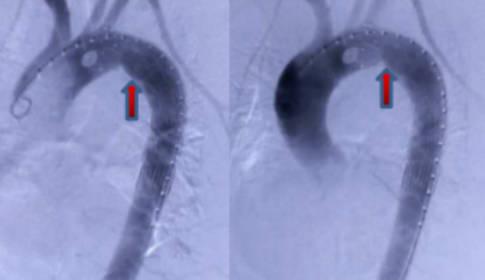

導讀 血管夾層是由于動脈中的血液,從血管內部破裂的地方進入了血管內外壁之間,而導致出現血管壁分離的現象,引起血管夾層的主要原因就是因為血管硬化。

血管夾層是由于動脈中的血液,從血管內部破裂的地方進入了血管內外壁之間,而導致出現血管壁分離的現象,引起血管夾層的主要原因就是因為血管硬化,當血管硬化,結果導致血管的彈性非常差,如果同時伴隨著患者還有突發性的高血壓癥狀,那么突發性高血壓,再加上血管彈性差,就很容易出現血管夾層。

如果患者突然出現了突發性的高血壓,那么血管在高壓的血流沖擊過程中就會被撕開,這個時候血液就會在開口處涌入血管的內層和外層之間導致其分離,血管夾層最常見的是胸主動脈血管夾層,因為在血液被心臟泵出之后,就會向流向下肢,然后再下肢開始分布,這個時候血流的沖擊是非常大的,很容易造成胸主動脈血管的撕裂,從而形成胸主動脈血管夾層,一旦出現此種情況,患者往往會伴隨著突發性的胸背部疼痛而且疼痛非常的劇烈,這種疾病的死亡率非常高。